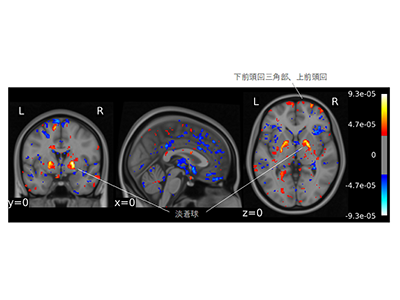

その結果、機械学習器の精度はテストデータセットで75%だった。さらに、独立確認データセットでも76%と精度を維持した。両側淡蒼球と下前頭回三角部は、慢性期統合失調症の分類に重要な特徴量を示した。統合失調症臨床病期群は、発達障害群と比較して慢性期統合失調症として分類された(慢性期統合失調症への分類率:精神病ハイリスク、41%;初回エピソード精神病、54%;慢性期統合失調症群、70%;発達障害群、19%;健常者群、21%)。

また、この機械学習器は、これまで統合失調症の脳病態と考えられてきた淡蒼球や下前頭回三角部などの重要性を改めて指摘した。これまでの機械学習研究では、既存の脳画像研究成果と整合性が取れず、その信頼性が疑問視されている部分があった。今回の機械学習器では、既存の脳画像研究成果との整合性も取れており、今後、機械学習解析を利用したさらなる病態解明も期待される。